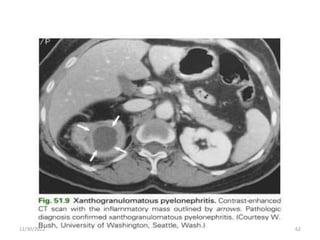

Xanthogranulomatous Pyelonephritis

• Xanthogranulomatous pyelonephritis is a poorly

understood, uncommon, but severe chronic renal

infection associated with obstruction of the urinary

tract.

• The renal parenchyma is replaced with a diffuse or

segmental cellular infiltrate of foam cells, which are

lipid-laden macrophages.

12/30/2022 58

Cont…

• Pathogenesis appears to be multifactorial, with

infection complicating obstruction and leading to

ischemia, tissue destruction, and accumulation of

lipid deposits.

12/30/2022 59

• Characteristically middle-aged women and have

chronic symptoms such as flank pain, fever, chills,

and malaise.

• Flank tenderness, a palpable mass, and irritative

voiding symptoms are common.

• The urine culture is usually positive with E. coli, other

gram-negative bacilli, or S. aureus.

• CT shows an enlarged nonfunctioning kidney, often

the presence of calculi and low-density masses

(xanthomatous tissue).

• Broad-spectrum antimicrobials are indicated, but

total or partial nephrectomy is usually necessary for

cure.